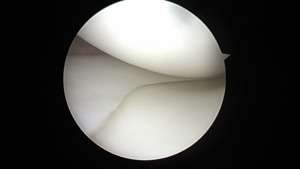

Physical examination of the patient’s left knee demonstrated passive range of motion that was 5 degrees shy of full extension with flexion to 130 degrees. She was 121 centimeters (3 feet 11 inches) tall and weighed 34 kilograms (74.8 lbs) with a BMI of 23.2. Her ligamentous knee exam was noted to be stable. She had tenderness over the lateral joint line and a sense fullness reported on the posterior aspect of her knee. Initial radiographs performed demonstrated normal anatomic alignment and did not reveal any bony hip or knee pathology (Figure 1).